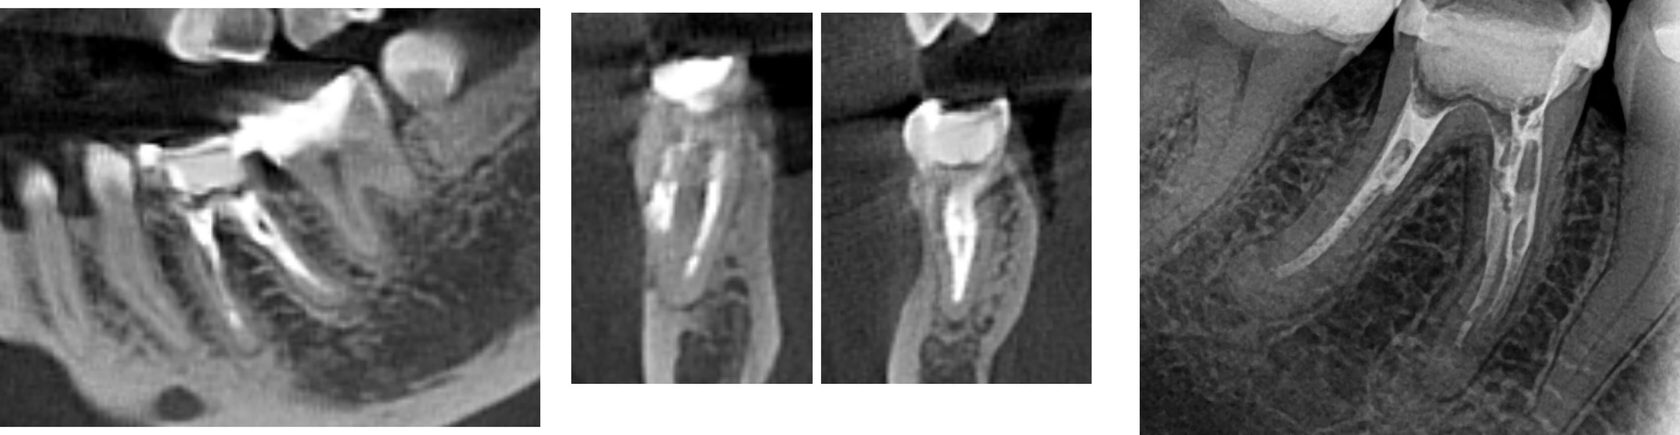

2. During the initial appointment, endodontic revision was performed, including the successful removal of the fractured instruments from the mesial root canals. The root canal system underwent thorough mechanical and chemical debridement, followed by temporary obturation with a calcium hydroxide-based medication for a two-week period to promote disinfection and periapical healing. (Image 4)